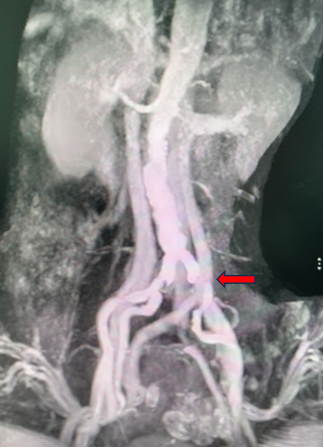

核磁检查影像:

动脉长鞘怎么置入桡胜一筹丨吴巍巍主任、赵俊来教授团队:应用Brite Tip RADIANZ长鞘经桡动脉治疗下肢动脉粥样硬化闭塞症一例_https://www.jmylbn.com_新闻资讯_第8张

左侧髂总动脉重度狭窄

ABI数值:

左侧 0.72

右侧 1.07